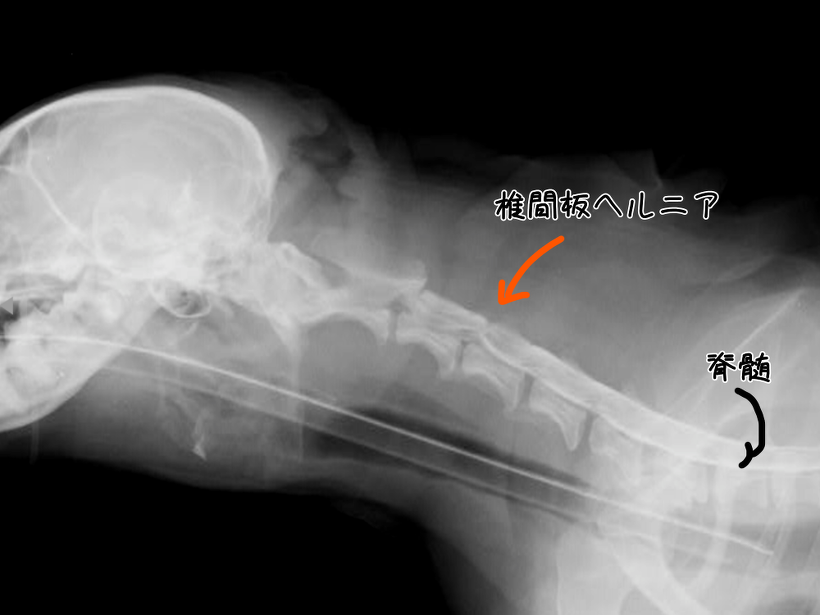

脊髄はX線では通常写りませんが、造影剤を入れることで浮かび上がらせることができます。

写真で首の骨の中に二重の線が見えるかと思います。

この部分が脊髄です。

そして、一部山なりに凹んでいる部分が、椎間板ヘルニアを起こして首の下の方から脊髄が押されている部分です。